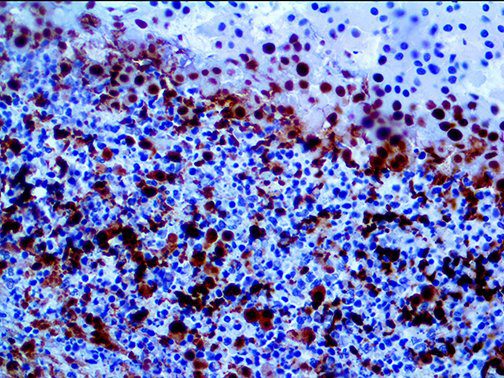

It is the ICU physician who is most likely to witness one of the deadliest manifestations of the abnormal immunological response, the cytokine storm syndrome (CSS). This response is also referred to by some as the cytokine release syndrome (CRS). CSS is characterized by continuous activation and expansion of macrophage and lymphocyte populations, which secrete large amounts of cytokines, causing the cytokine storm. This massive cytokine release is akin to hemophagocytic lymphohistiocytosis (HLH) disease, a syndrome characterized by initial unchecked and persistent activation of cytotoxic T lymphocytes and NK cells.

Clinical and laboratory manifestations of HLH include fever, enlarged liver and/or spleen, neurologic dysfunction, coagulopathy, liver dysfunction, cytopenias (i.e., low levels of erythrocytes, leukocytes, and/or platelets), hypertriglyceridemia, hyperferritinemia, hemophagocytosis, and eventually diminished NK cell activity as the immune system becomes progressively paralyzed. HLH can be familial (primary HLH) or secondary to another disease process (sHLH), such as rheumatic disease, in which it is referred to as macrophage activation syndrome (MAS, characterized by elevated ferritin).